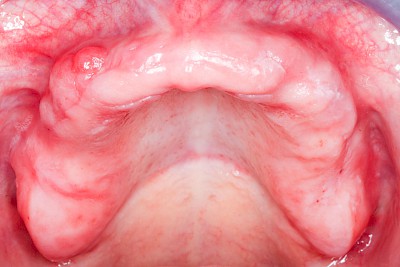

Schwellung ohne Eiter: faltenförmig

Als Sonderform des Reizfibroms können bei Zahnprothesen in den Randbereichen selten am Gaumen, häufiger außen in den Umschlagfalten in Ober- und Unterkiefer auch lappenartige Auffaltungen (Lappenfibrome) beobachtet werden, die ebenfalls aufgrund eines mechanischen Dauerreizes entstehen. Alle diese Veränderungen sind in der Regel eher wenig schmerzhaft – auch wenn man darauf drückt. Hier sollte zeitnah mit einem Zahnarzt eine Abklärung erfolgen.